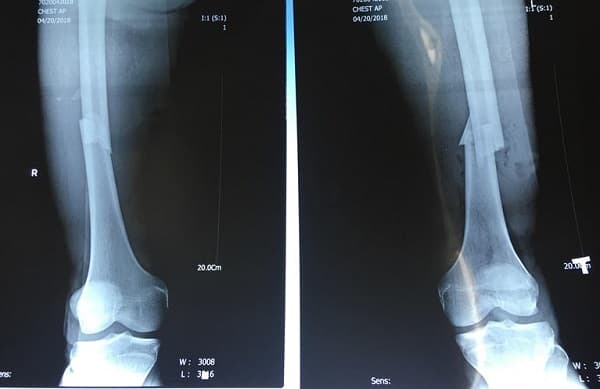

3.2. Điều trị ngoại khoa

Phẫu thuật để cố định phần xương bị gãy. Bác sĩ sẽ sử dụng ốc vít, thanh hoặc tấm theo để cố định xương cẳng chân với nhau.